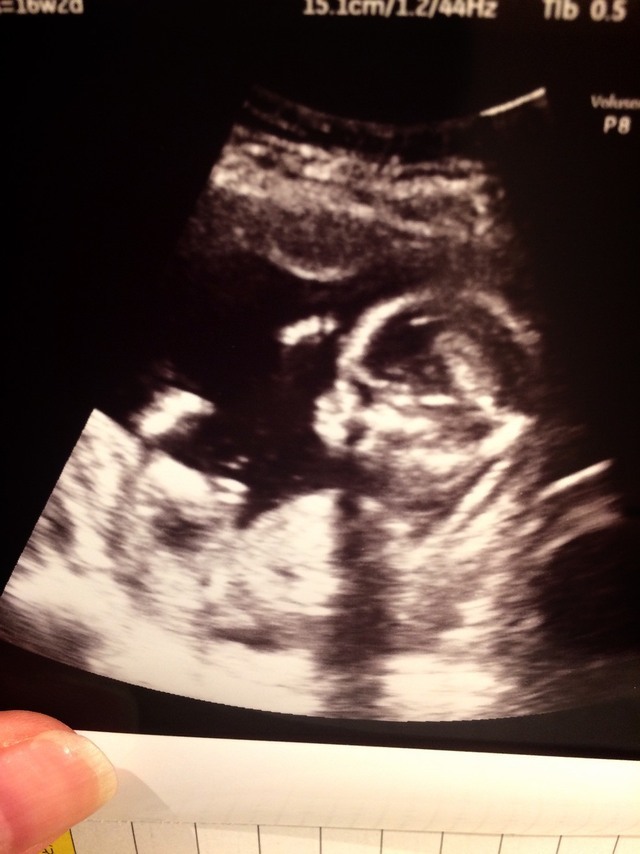

16週0日(16w0d・女の子)|ちーーさん さん(26歳)

エコー写真撮影時のエピソード:

なかなか顔を見せてくれず常に足か手で顔隠してたんですが、この時やっと顔見せてくれて主人とどっち似かね~って話したりしました。

義母は、「最近のエコー写真凄いね。昔は、はっきり分かりにくいしこんなのなかったよ」と4D写真にびっくりしてました。